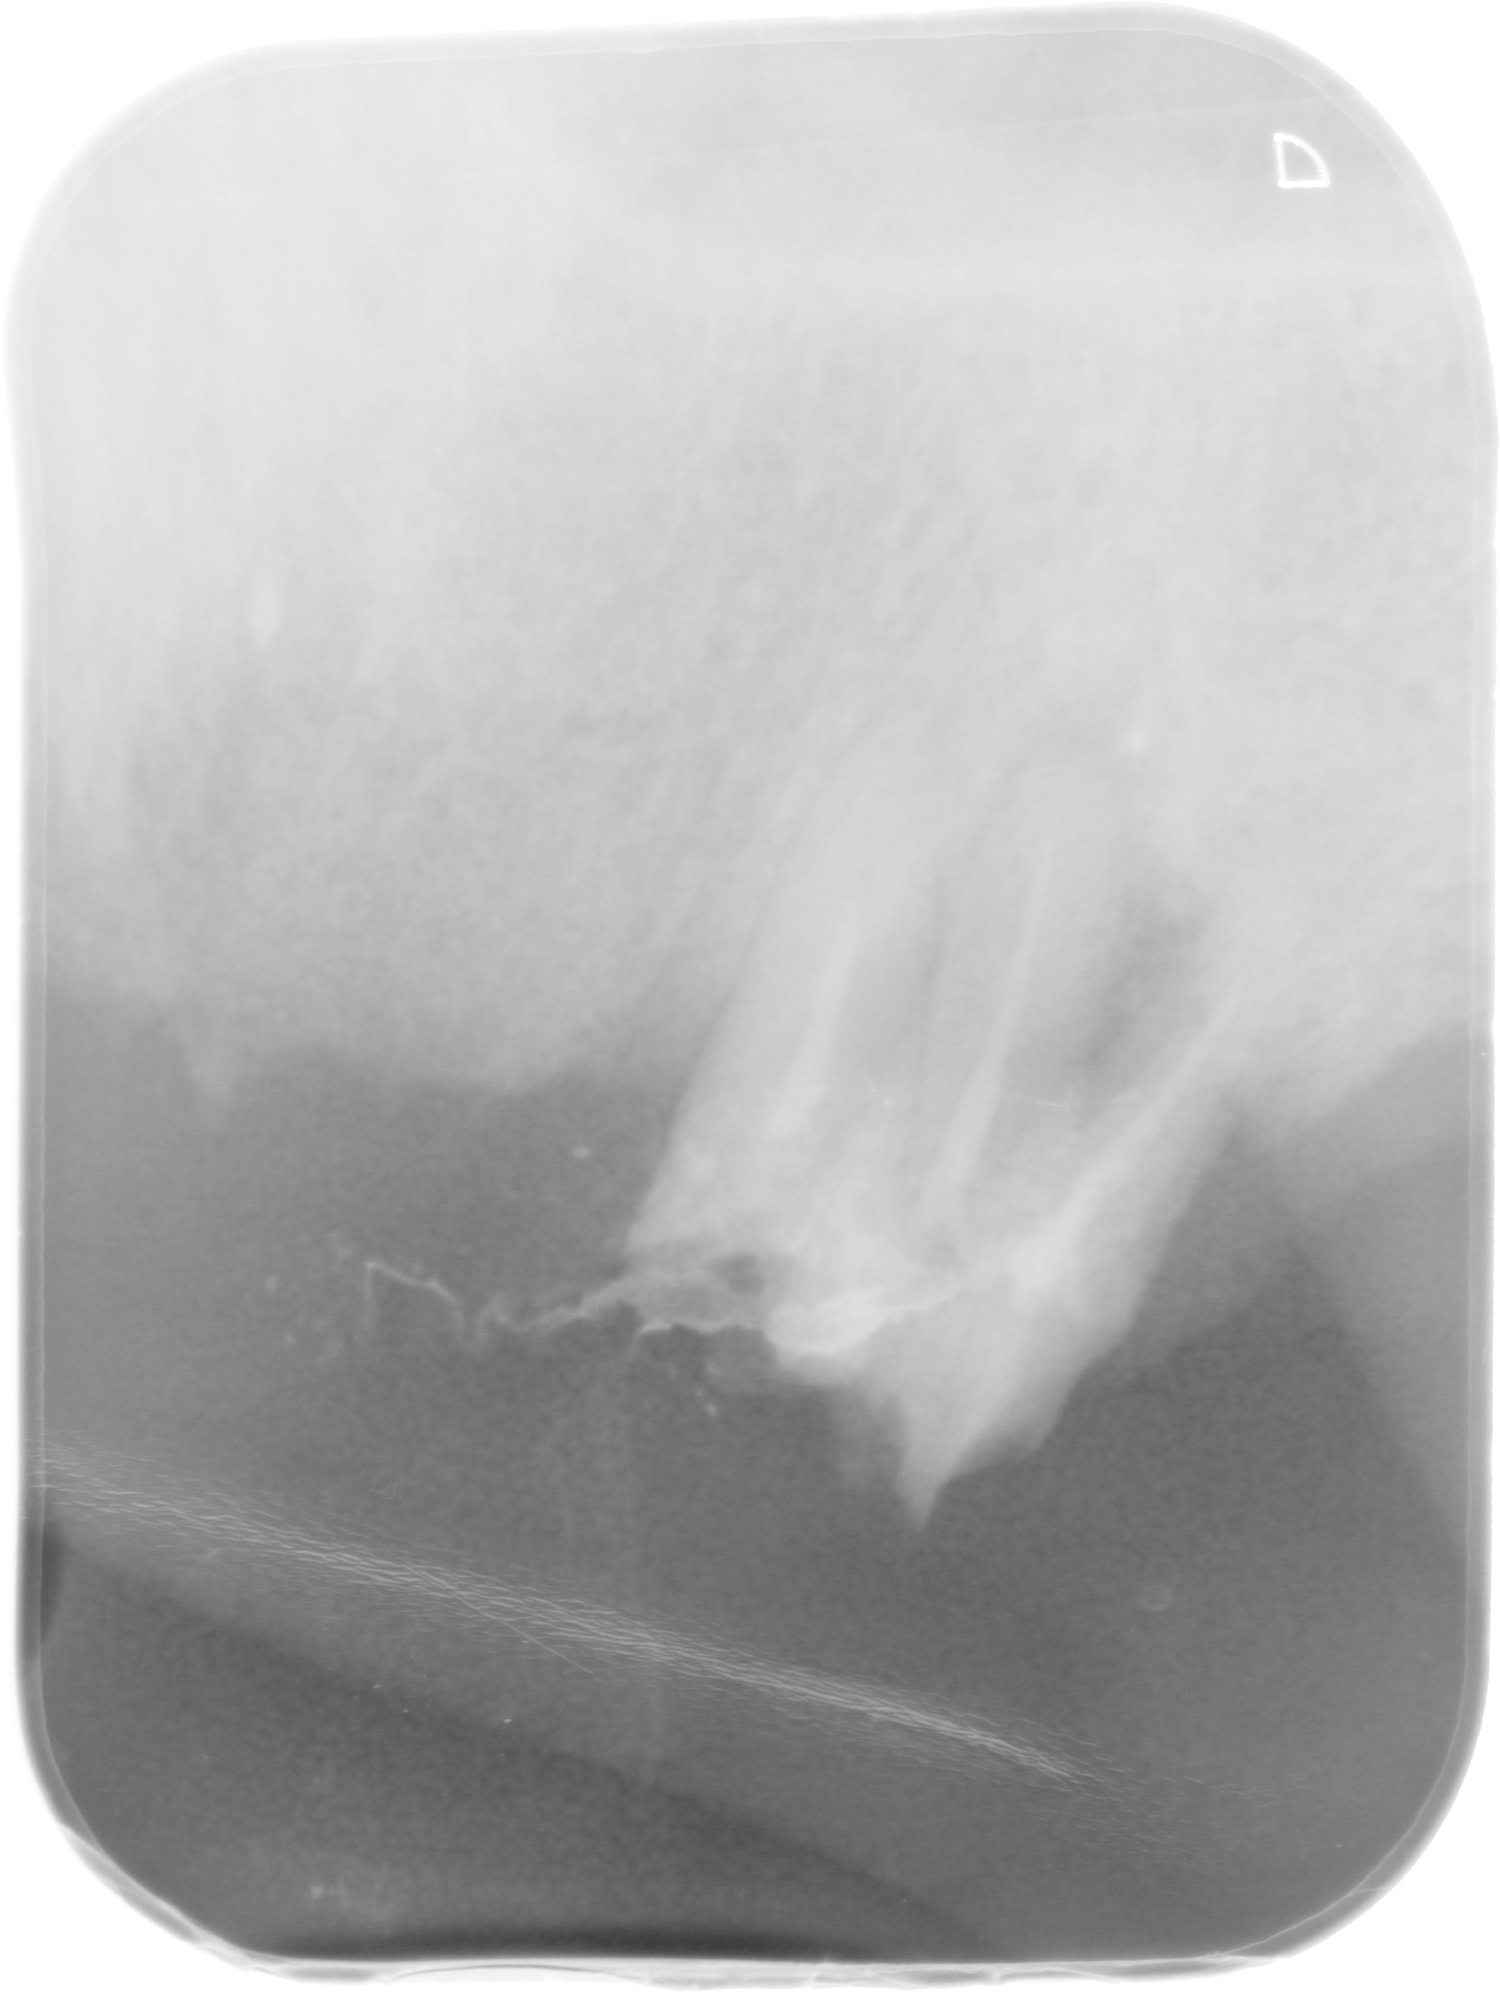

patient vu lundi: bridge ceram 7 éléments sur 24/23/11/13. Stellite derriere.

Boulot fait il y a un an 1/2.

Stellite cassé en deux au bout de 6 mois: réponse de la consoeur "j'y suis pour rien, faut refaire et repayer"

Le bridge je l'ai déposé car 24/23 sont complétement pourries, il ne tenait plus que par l'inlay core de la 13.

11 et 13 ont des endos à refaire et peut être pourrais-je les conserver comme overdenture sous le complet à venir, si j'arrive à déposer le morceau d'ic cassé dans la 11.

D'après le patient l'ic de 11 a cassé le jour de la pose mais ça a été posé et payé quand même....